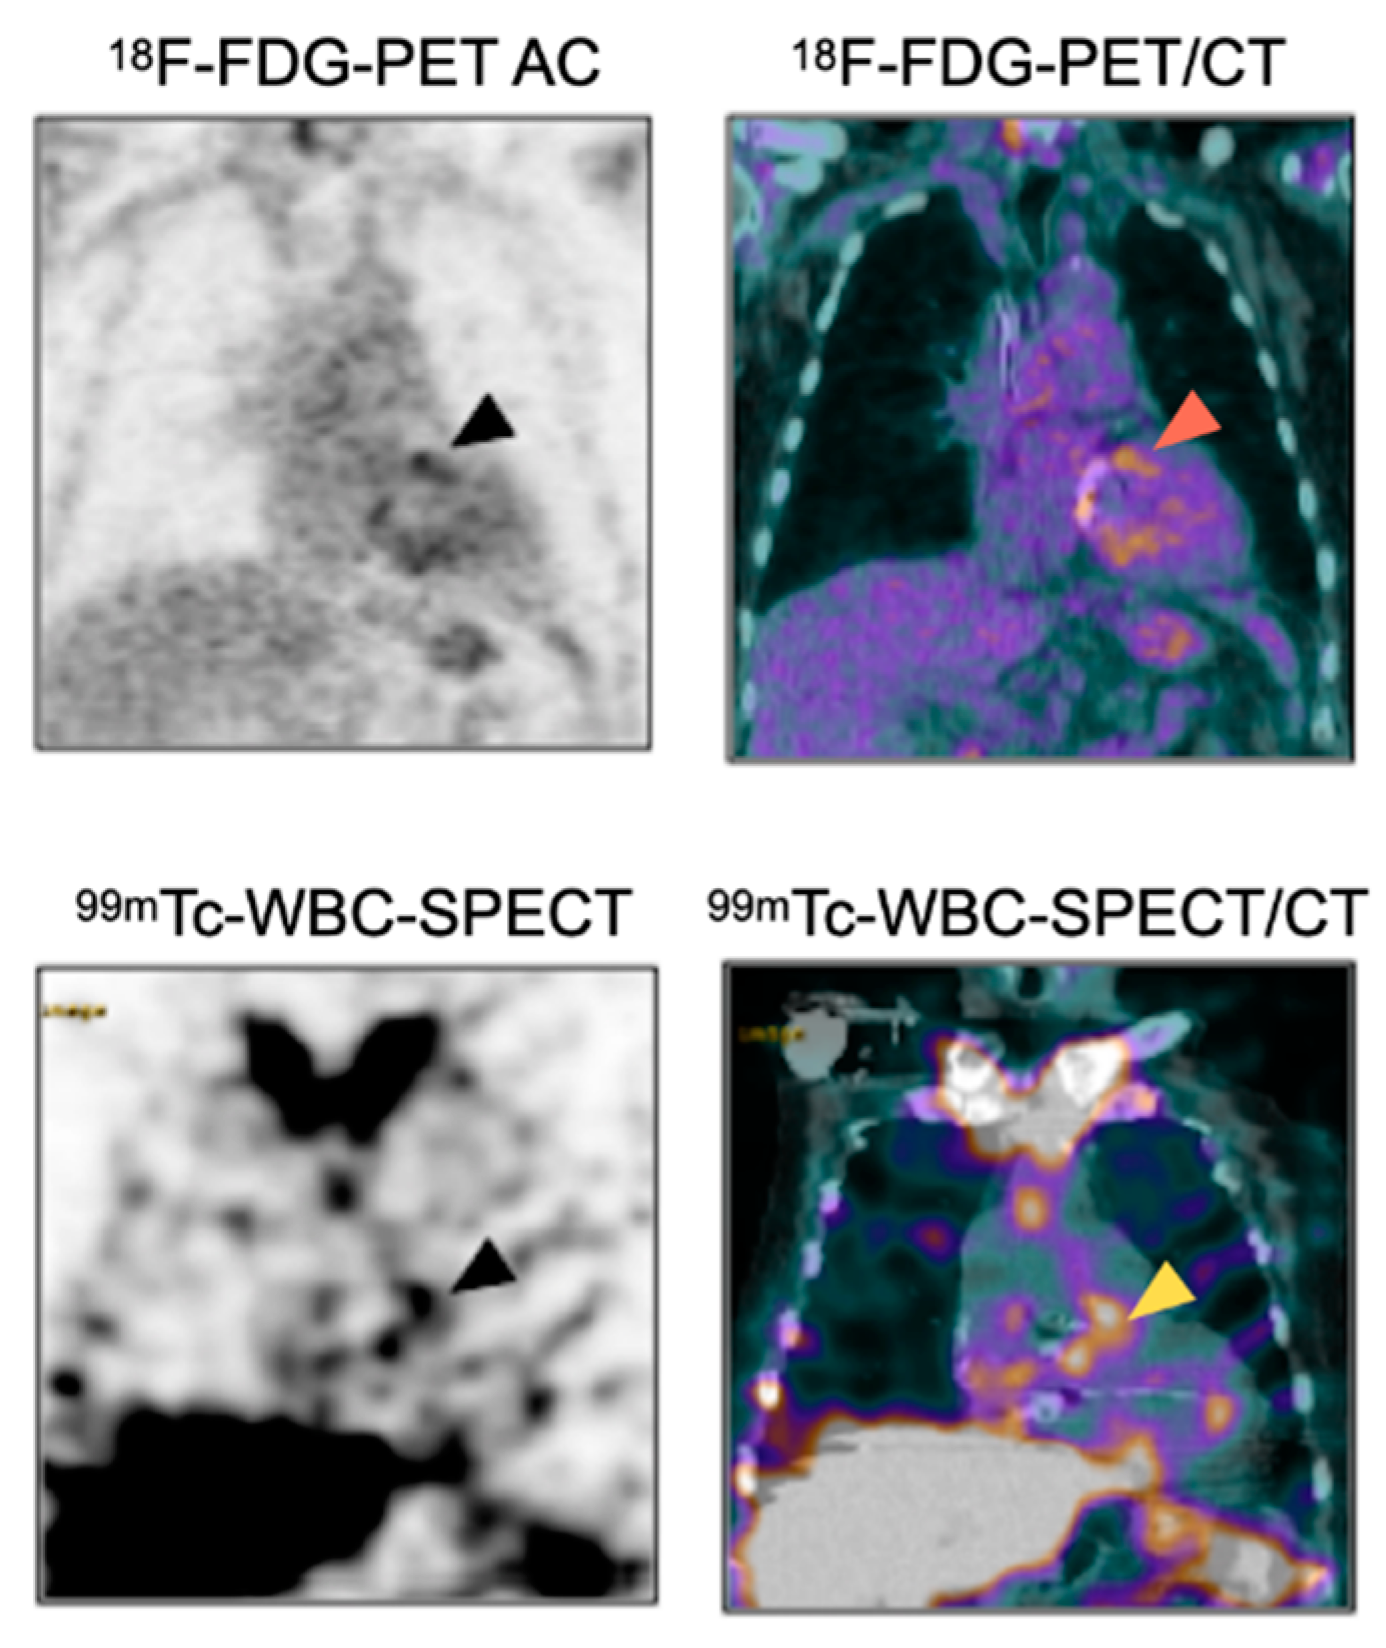

- Rouzet, F.; Chequer, R.; Benali, K.; Lepage, L.; Ghodbane, W.; Duval, X.; Iung, B.; Vahanian, A.; Le Guludec, D.; Hyafil, F. Respective performance of 18F-FDG PET and radiolabeled leukocyte scintigraphy for the diagnosis of prosthetic valve endocarditis. J. Nucl. Med. 2014, 55, 1980–1985. [Google Scholar] [CrossRef] [PubMed]

- Lauridsen, T.K.; Iversen, K.K.; Ihlemann, N.; Hasbak, P.; Loft, A.; Berthelsen, A.K.; Dahl, A.; Dejanovic, D.; Albrecht-Beste, E.; Mortensen, J.; et al. Clinical utility of (18)F-FDG positron emission tomography/computed tomography scan vs. (99m)Tc-HMPAO white blood cell single-photon emission computed tomography in extra-cardiac work-up of infective endocarditis. Int. J. Cardiovasc. Imaging 2017, 33, 751–760. [Google Scholar] [CrossRef]